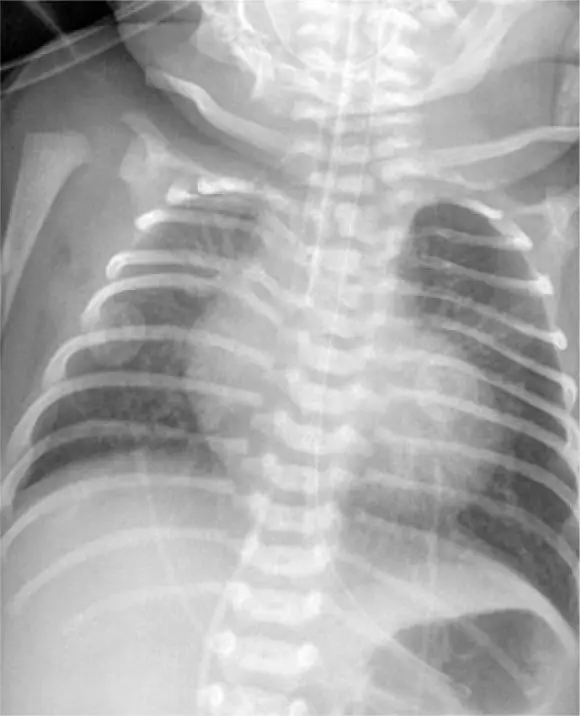

RESUMO O aneurisma gigante da artéria esplênica constitui condição rara, que representa risco de vida iminente para o paciente, necessitando, consequentemente, de correção cirúrgica urgente. Mulher de 61 anos, ex-fumante, hipertensa, com hipercolesterolêmica e multípara nos procurou por apresentar grande tumor no mesogástrio, achado de ultrassonografia abdominal. Apesar das dimensões do tumor, era assintomática. Angiotomografia e ressonância magnética de abdômen sugeriam tratar-se de aneurisma gigante de artéria esplênica com mais de 10cm de diâmetro, confirmado por angiografia. Foi submetida a […]